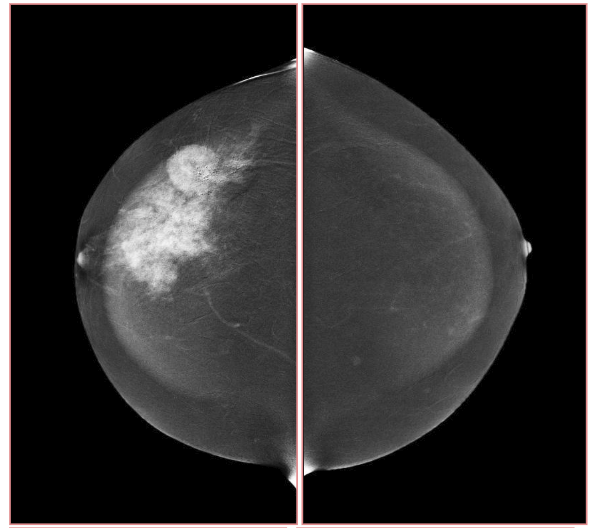

Digital breast tomosynthesis (DBT) is a promising new technology for acquiring and displaying three-dimensional mammograms [17]. Because of its improved ability to differentiate true breast lesion or summation of normal breast structures. An example image of tomosynthesis is shown in Fig. 3, for the different planes, it has improved characterization of masses. Tomosynthesis is increasingly being used in the diagnostic setting to evaluate masses, asymmetries, and architectural distortion. Tomosynthesis can be done in full or spot compression views as needed [18]. The sensitivity and specificity of DBT ranged from 74.2% to 86.9% and 97.0% to 97.5%, respectively [19].